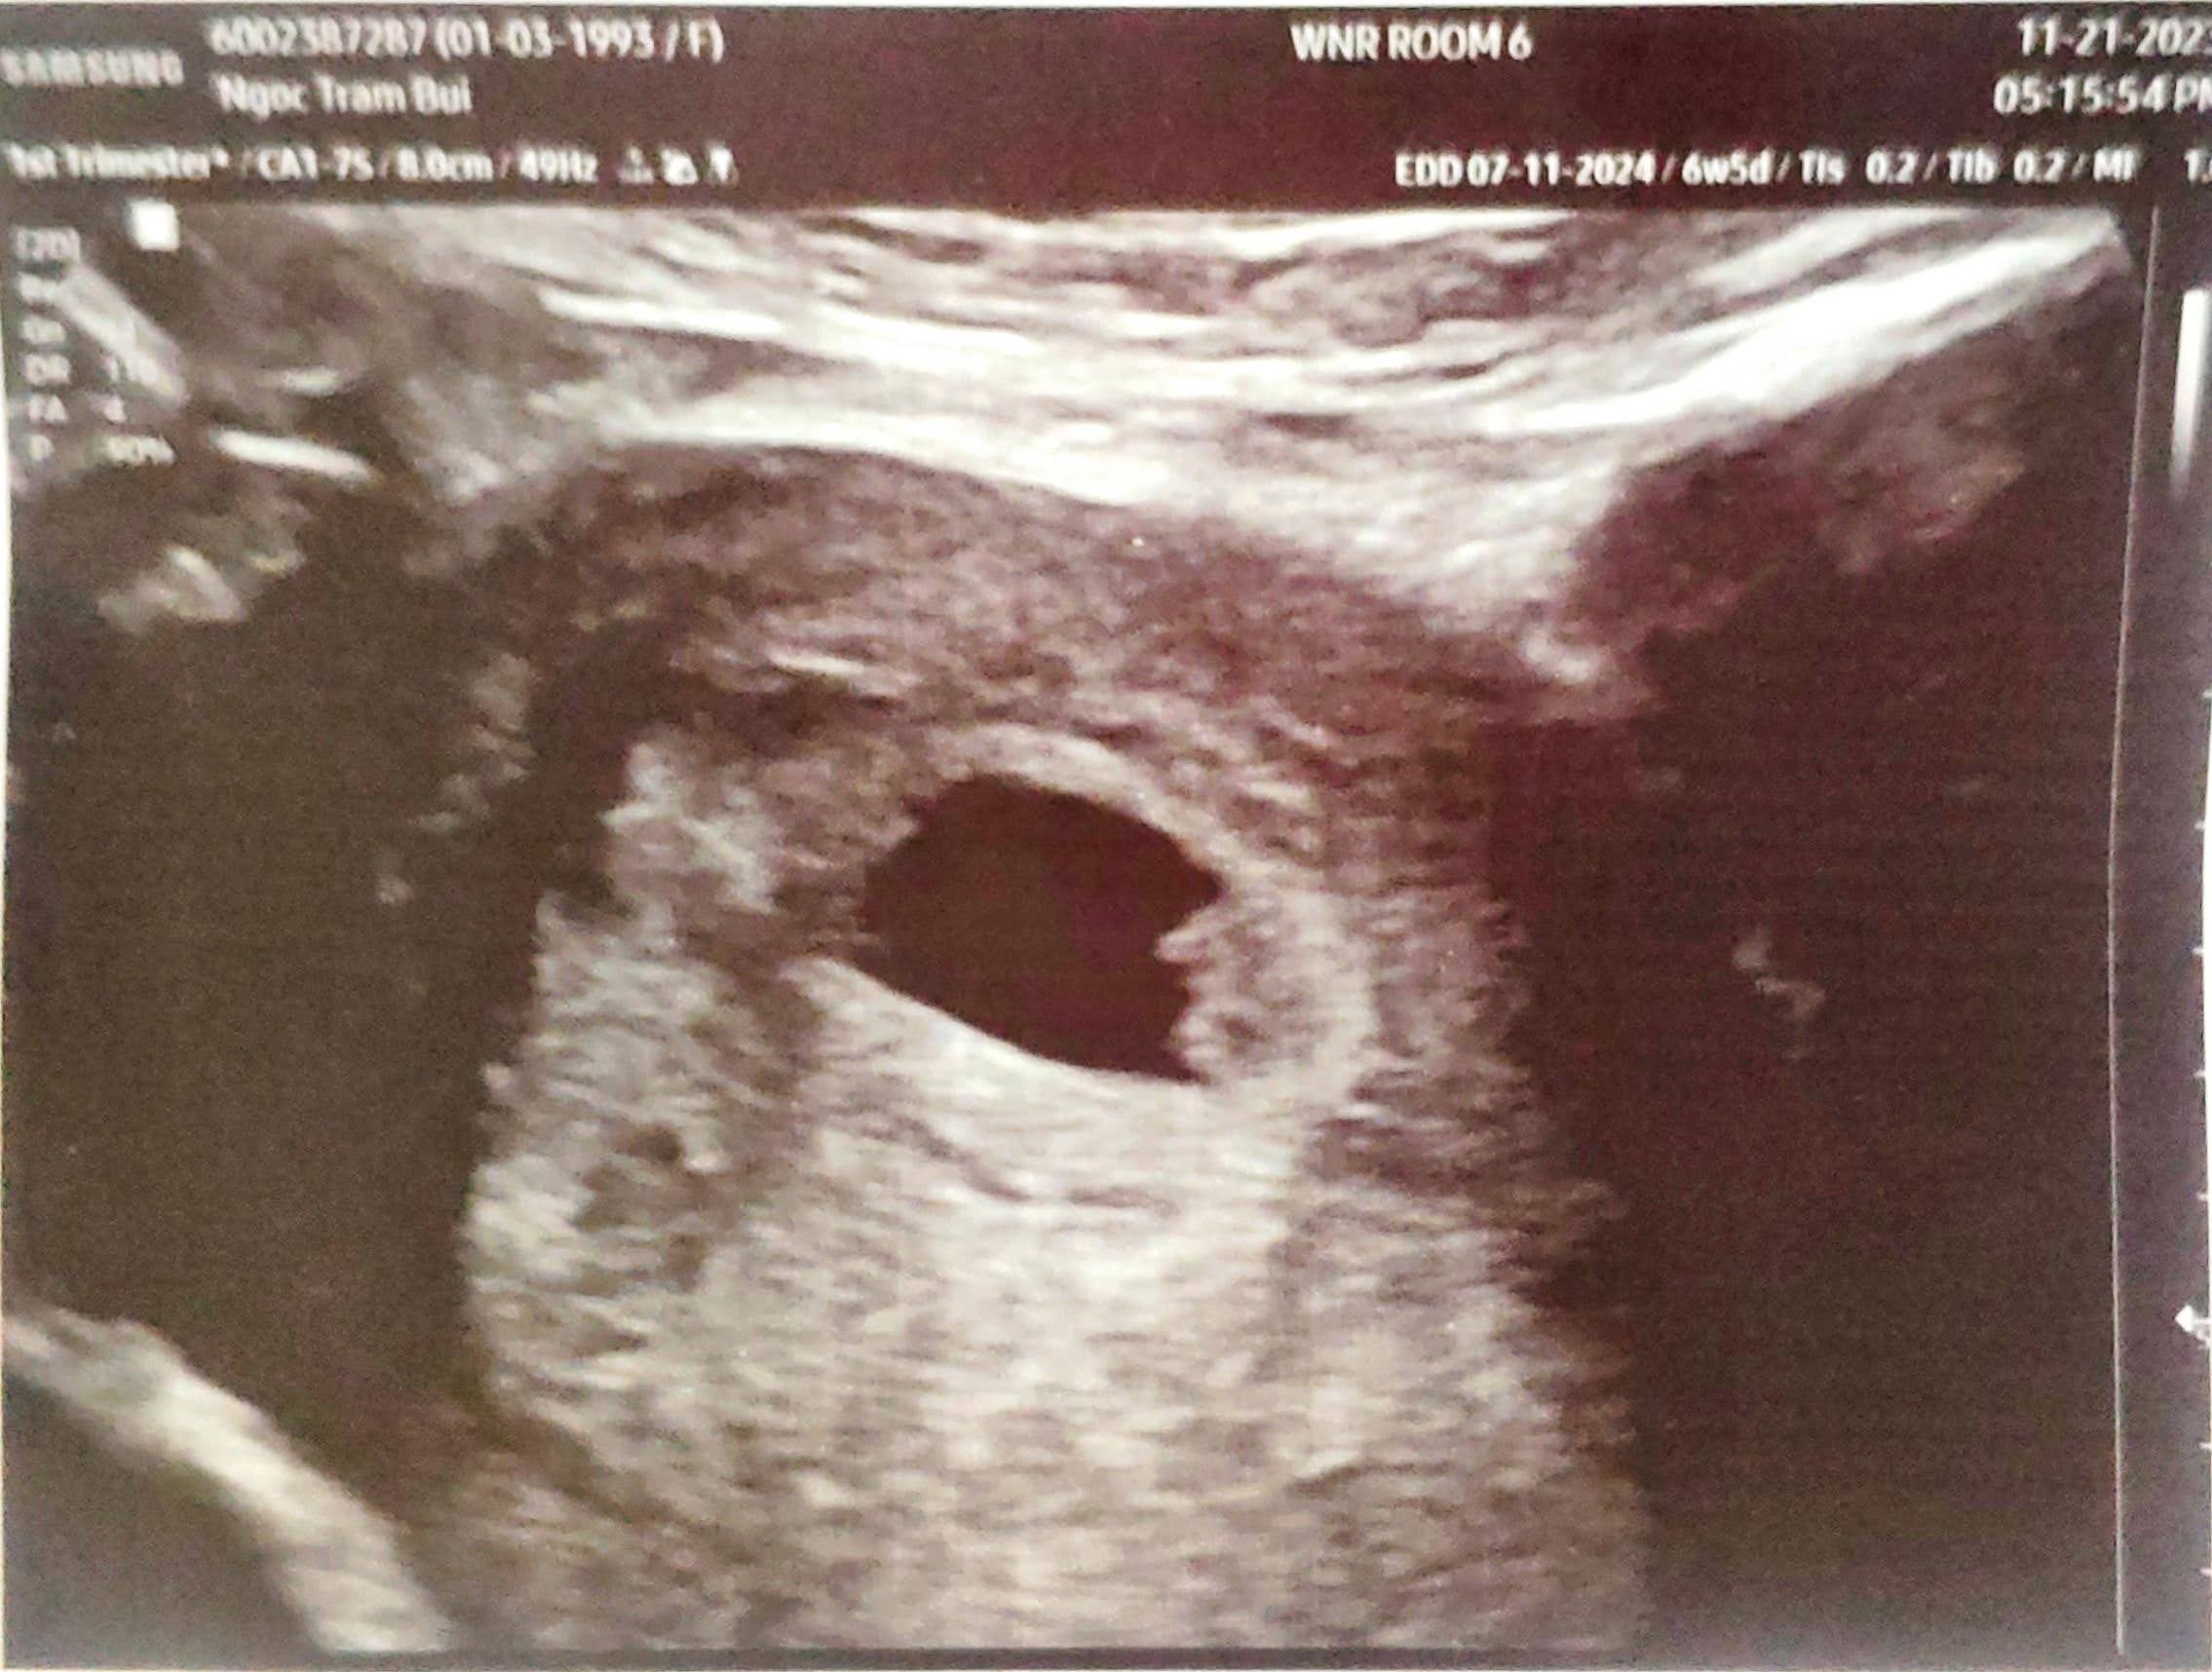

2. Đi ultrasound

7 Nov 2023

Một ngày mà hoàn tất xét nghiệm máu và siêu âm. Niềm vui khôn xiết vì đã thấy được tim thai